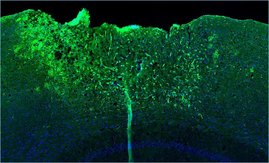

„Mit hochauflösenden mikroskopischen Verfahren konnten wir an menschlichen Glioblastomen in Mausgehirnen beobachten, dass diese Krebszellen sich nach dem gleichen Muster durch das Gehirn bewegen wie Raubtiere auf der Suche nach Beute durch ihr Revier – ähnlich wie Nerven-Vorläuferzellen. Dabei scannen sie mit feinen Zellausläufern die Umgebung und erhalten über ihre Synapsen aktivierende Signale der Nervenzellen, die sie für die Invasion zu brauchen scheinen“, beschreibt Prof. Kuner. Sein Team nutzte eine Kombination moderner mikroskopischer und molekularbiologischer Methoden, die detaillierte und dreidimensionale Blicke auf das Verhalten der Zellen im Gewebe, ihre Zell-Zell-Kontakte sowie ihre molekularen Eigenschaften lieferten.

Unter dem Mikroskop zeigte sich: Nachdem die ausschwärmenden Zellen einen günstigen Platz gefunden haben, verändern sie ihre molekularen Eigenschaften und verwandeln sich in einen Zelltyp, der sich nicht mehr bewegt, sondern Netzwerke ausbildet. „Das Verhalten gleicht der Kolonisierung eines neuen Kontinents: Erst ziehen einzelne Siedler los in die Weite, nehmen Kontakt mit den Einheimischen auf und werden sesshaft.“, beschreibt Erstautor Dr. Varun Venkataramani.